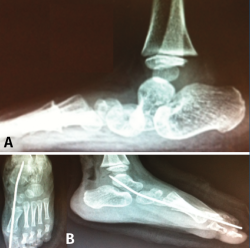

Figura 16. A: valgo severo de retropié secundario a coalición talocalcánea; B: tras resección completa por vía artroscópica de la coalición, se verifica la movilidad subastragalina, al realizar varo-valgo del talón; C: colocación de calcáneo stop, para corregir el valgo del retropié; D: tomografía axial computarizada de control, donde se visualiza resección de la coalición y corrección del valgo del retropié.